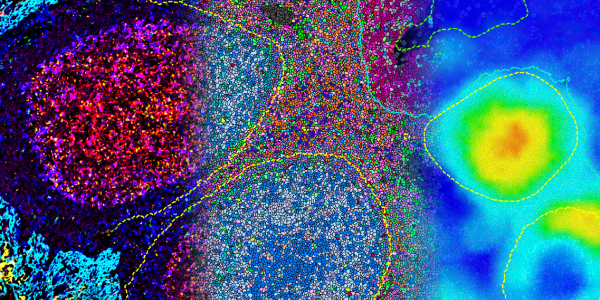

Multiplex Immunofluorescence

HALO

Digital pathology image analysis platform for phenotyping, cell quantification, and spatial analysis in research and clinical settings.

HALO AI

AI-enhanced module for HALO, improving accuracy and speed in image analysis through deep learning technologies.